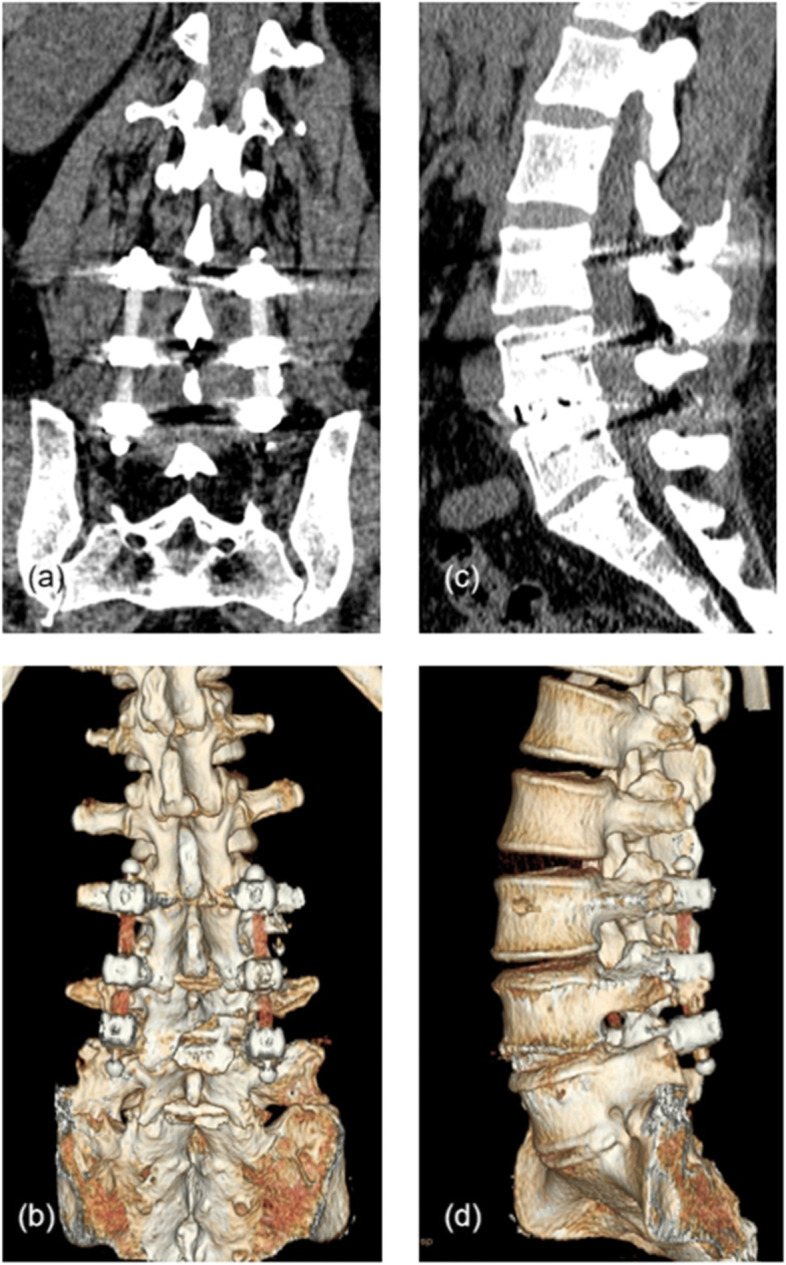

Fig. 3.

Typical case. a, b Coronal lumbar CT scan and 3D reconstruction taken at the 2-year follow-up, showing the contours of the bilateral PEEK rods. c, d Sagittal plane image and 3D reconstruction showing intervertebral fusion was achieved at the L4/5 segment